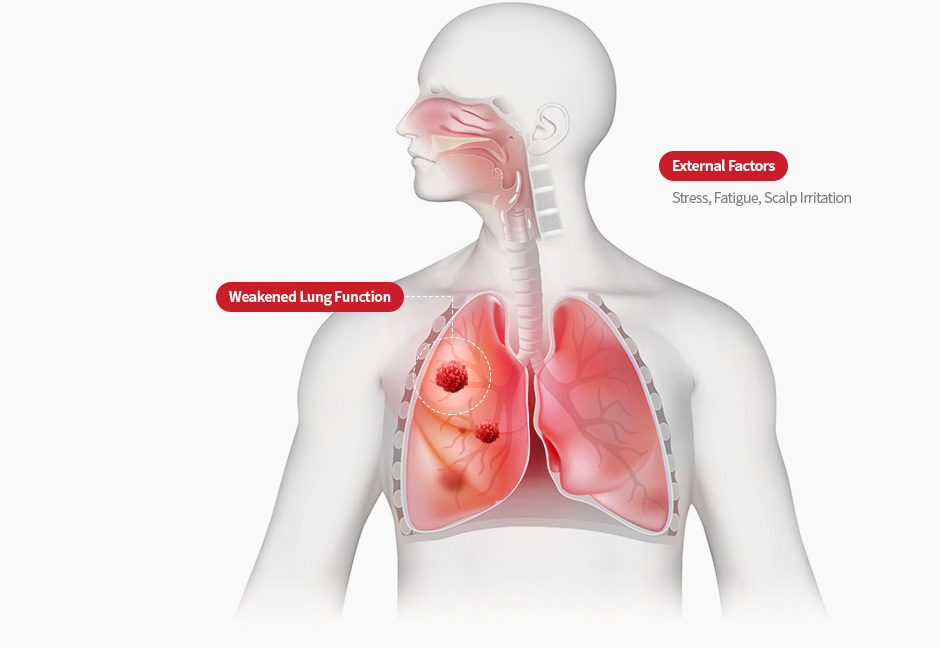

Scalp inflammation can cause significant hair loss.

Avoid alcohol and overexertion to manage the condition,

and seek proper treatment when early symptoms like dandruff or itching appear.

It's important to reduce physical fatigue and mental stress.

Psychological stress and overwork can worsen the condition,

so it’s important to stay calm and relaxed.